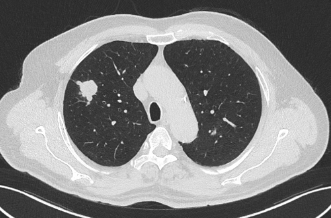

术前患者CT

近日,昭通市中医医院呼吸与危重症医学科二科成功为一名合并多种基础疾病的61岁肺癌患者实施了昭通首例经口支气管镜超声(EBUS)引导下肺癌冷冻消融术。该患者因“反复咳嗽、咳痰1年,确诊右肺鳞癌2月余”入院。胸部增强CT显示其右肺上叶存在两个高危结节(Lung-RADs 4X类),同时合并慢性支气管炎伴肺气肿、肺炎、冠心病(支架术后)、肺大疱、肺不张等疾患。